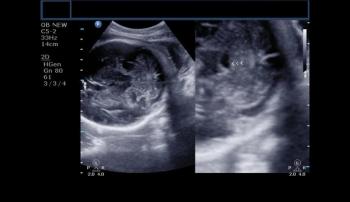

Name the structure arrowed in this normal fetal brain in a 35-week fetus.